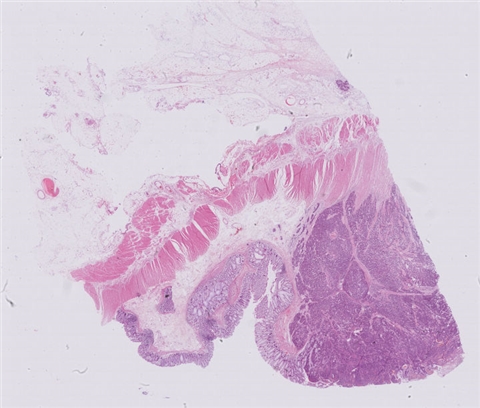

患者详情: 患者于半年前无明显诱因出现大便带血,为暗红色血便,未见粘液脓血便,反复发作,无腹痛腹胀,伴大便次数增多,并大便不成形,逐渐变细,初未引起重视,亦未行相应治疗,后症状逐渐加重。为进一步诊治,2020年3月入住我院。 直肠指诊:括约肌紧张度:正常,狭窄:无,触痛:无,距离肛门口大约4cm可及一环直肠一周肿块,质硬,移动度差,无压痛,指尖稍可通过肿块,指套染血:有。 电子肠镜示:距肛门4cm直肠处可见一巨大新生物,中间凹陷,底覆污秽苔,环2/3腔生长,钳取6块送病理,余 结肠各段粘膜光整,血管纹理清晰,未见明显的溃疡、息肉。 活检病理示:恶性肿瘤。后行腹腔镜直肠癌根治术。

大体所见: 1、直肠癌肿物:已切开肠管一段,长10cm,一侧切缘周长4cm,另一侧切缘已缝合,长3cm,紧邻缝合切缘见一溃疡型肿物,大小4.5*4*3cm,肿物切面灰白灰黄色、质硬,与周围组织分界欠清,侵及全层。